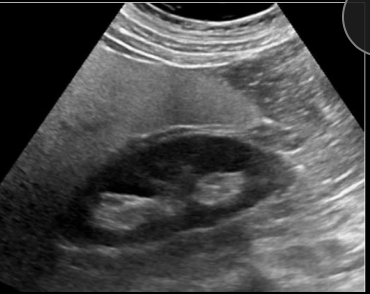

3

Q

A

probable hígado graso